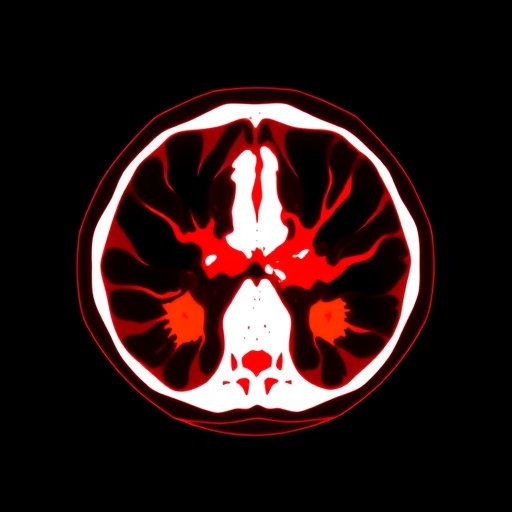

Utilizing a biofidelic model that closely mimics real human anatomical structures, the researchers focused on creating a high-fidelity representation of individuals experiencing sideways falls. This model not only simulates the fall motion with remarkable accuracy but also allows for the assessment of various injury scenarios, such as fractures and soft tissue damage. The researchers emphasized that the realism of the biomechanical model is critical for reliable predictions of injury risk.

To address the limitations of CT scan coverage, the team developed an automated workflow that streamlines the process from data acquisition to model generation. This workflow employs novel algorithms that integrate multiple imaging modalities, ultimately enhancing the anatomical detail available for simulations. The optimization of this workflow is particularly vital in clinical settings where rapid decision-making during trauma cases is essential.

One of the standout features of this research was the detailed analysis of the forces and moments acting on the body during a sideways fall. By applying the FE model, the researchers were able to simulate the stress distribution across different skeletal structures and soft tissues. The team meticulously documented how variations in fall angles and surface conditions influenced injury outcomes, providing invaluable information for fall prevention strategies.